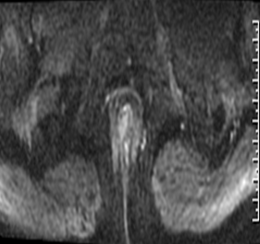

(MRI影像示意图,展示肛瘘常见表现)

在MRI图像中:

◆ 活动期肛瘘MR常表现为T2WI高信号,增强明显强化;

◆ 寻找内口以T1WI增强序列最佳,其次为T2WI抑脂序列,内口影像表现为括约肌内点状T2WI高信号,明显强化或括约肌受牵拉,括约肌间隙消失;

◆ 直径<1CM为瘘管,瘘道的管径最宽处直径>1CM的局限膨隆为脓肿;

◆ 肛瘘愈合期或慢性期,T2WI常表现为低信号,强化减弱或无强化。